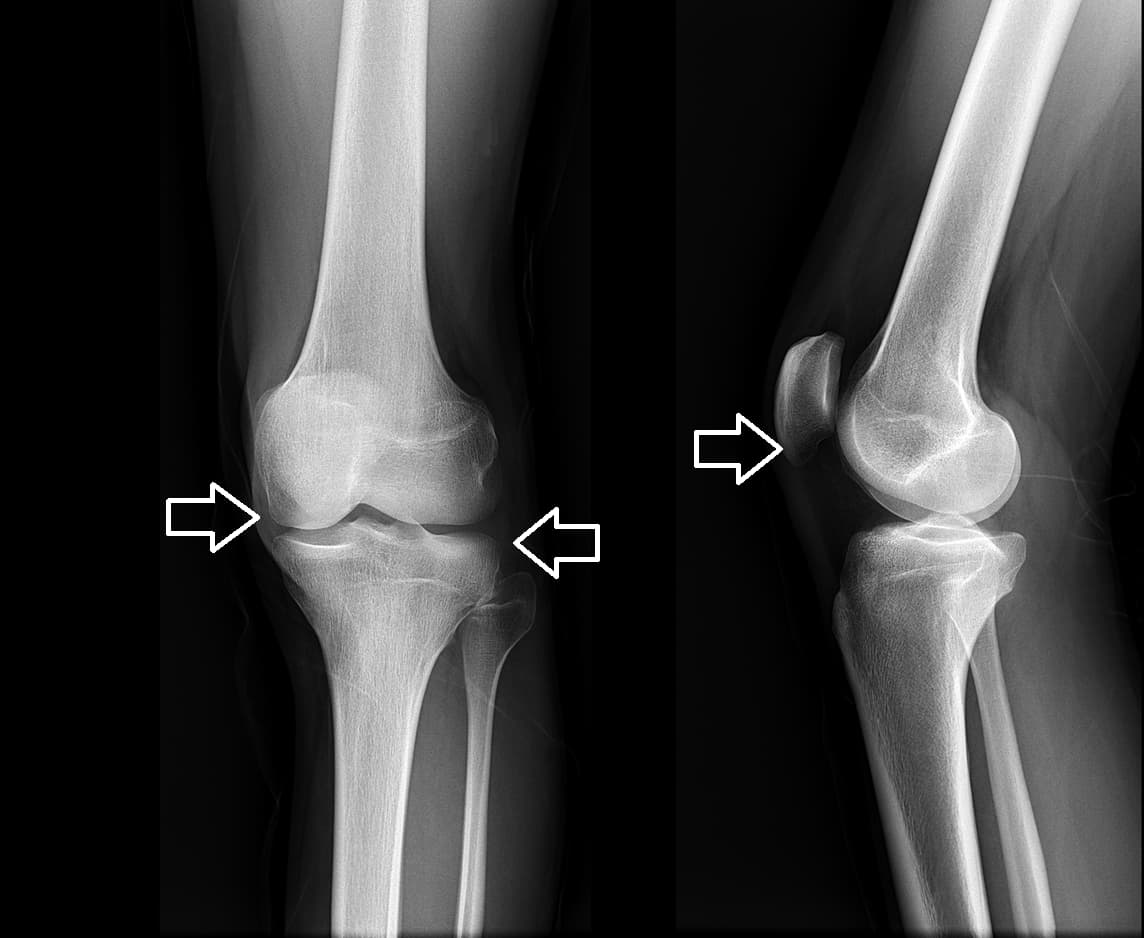

така се надявах... Без повече приказки ми направи пълен преглед, който включваше

рентгенови снимки и

изследвания на кръв и урина.

При следващото посещение, буквално в

рамките на няколко минути,

тя ми постави диагноза вторичен

остеоартрит с

направиха рентгенови снимки. Никакви признаци на остеоартрит! Хрущялите в

ставите ми бяха като на

20-годишно момиче. Лекарят реши, че предишната рентгенова снимка вероятно е била

с дефект, така че

диагнозата остеоартрит е била погрешна.